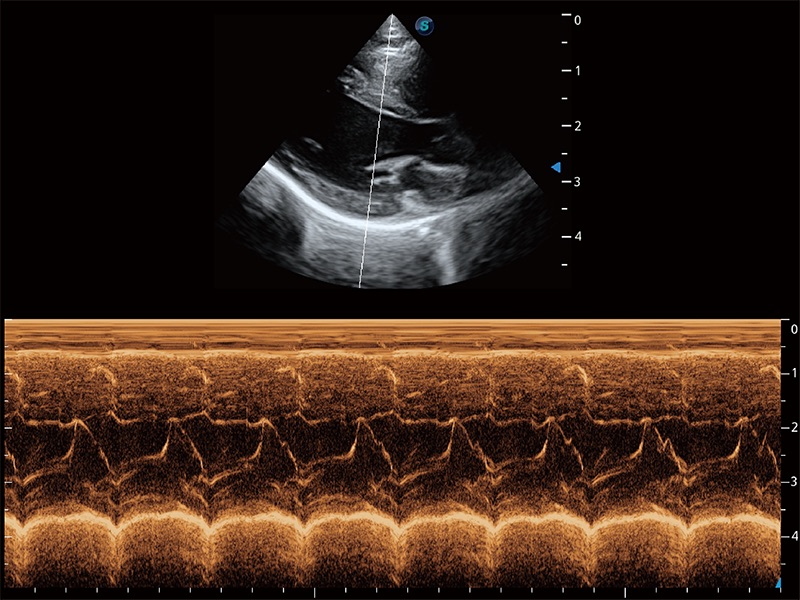

(猫)二尖瓣M型

(犬)二腔心血流